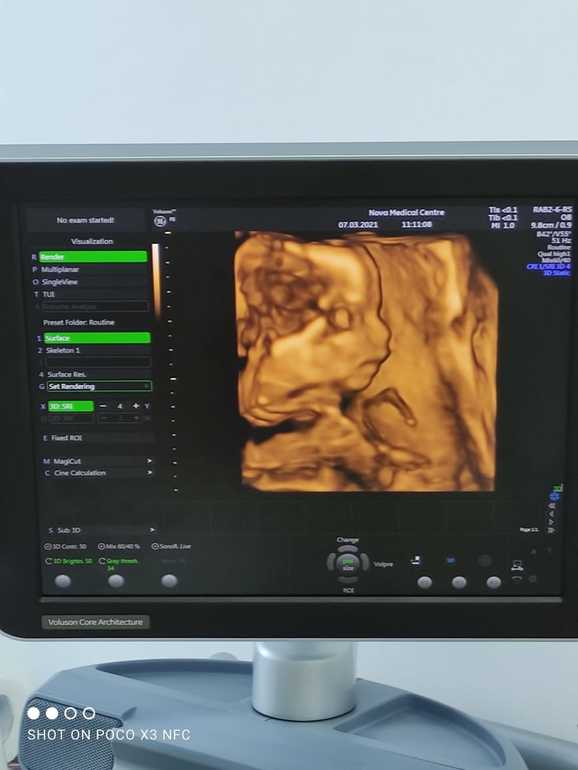

Анализы все в норме, 7 марта прошла 2 скрининг с малышом все отлично, пинается во всю, правда больше пинки начинаются ближе к ночи, папуля наш умиляется когда кладёт руку на животик потому что малышастик пинает 🙂🥰

И так наша эпопея с определением пола началась с 1 скрининга мы очень хотели узнать кто живёт у нас в домике, я в глубине души была настроена на доченьку т.к первый сыночек уже есть, муж со дня полосатого теста говорил что второй тоже будет сынок(🤣Ванга блин) и наконец-то нам окончательно и 100% сказали что у нас будет второй Мальчик ❤️🥰мы безумно рады (я конечно погрустила) , но потом муж сказал в третий раз точно пойдём за доченькой😂, а так буду наслаждаться мужским вниманием и если что внучек буду воспитывать😂 для себя сделала вывод что раньше второго скрининга не заморачиваться про пол🙂